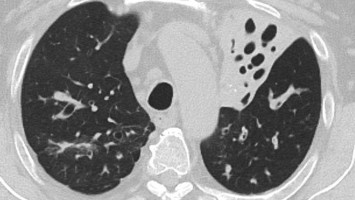

Wenn der Husten in die Jahre kommt: Alles nur Asthma?

Ein 65-jähriger hausärztlich tätiger Kollege stellt sich wegen zunehmender Belastungsdyspnoe, chronischem Husten mit produktivem Auswurf und abendlichen subfebrilen Temperaturen vor. Seit Jahren ist ein allergisches Asthma bekannt, zudem liegt eine chronische Kolonisation mit Pseudomonas aeruginosa vor. Die Ursache seiner Beschwerden liegt jedoch woanders.

e.Med Interdisziplinär Icon, Search Icon, Transvaginaler Ultraschall/© Graphicroyalty / stock.adobe.com (Symbolbild mit Fotomodellen), Glaszellentumor der Gebärmutter/© Boeker M et al. / all rights reserved Springer Medizin Verlag GmbH, Extrauteringravidität /© Tsitlakidis I et al. / all rights reserved Springer Medizin Verlag GmbH, Bilaterale ausgedehnte zylindrische Bronchiektasen/© Düsterhöft D et al. / all rights reserved Springer Medizin Verlag GmbH, CT des Uterus einer 47-Jährigen /© Rizos A et al. | all rights reserved Springer Medizin Verlag GmbH, MRT des Beckens: Uterus und Ovarialtumoren/© Hosten AK et al. / all rights reserved Springer Medizin Verlag GmbH, Digitales Blutdruckmessgerät/© Kotchakorn / Stock.adobe.com (Symbolbild mit Fotomodell), Frau tastet ihre Brust ab/© Pheelings Media / Getty Images / iStock (Symbolbild mit Fotomodell), Feten von siamesischen Zwillingen/© Zahn E et al. / all rights reserved Springer Medizin Verlag GmbH, MRT einer intrakavitären Raumforderung/© Lattermann M et al. doi.org/10.1007/s00761-025-01733-0 unter CC-BY 4.0, Aufnahme nach Resektion der Extrauteringravidität/© Antonia Jörger